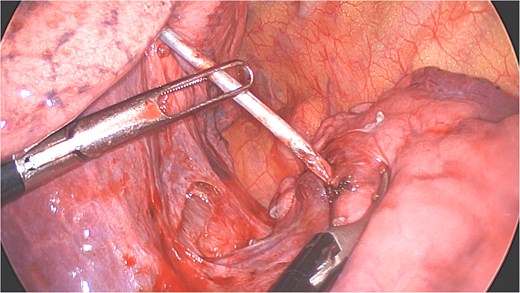

Under general anesthesia with a left double-lumen intubation a left thoracoscopy (VATS) was done using one 11 mm trocar and 2 trocars of 5 mm and a 30° 5 mm camera. We saw a pleural cavity with dense apical adhesions of the left upper lobe against the inferior border of the clavicle (Fig. 3).

Perioperative views of the migrated K-wire, showing dense apical adhesions of the left upper lobe.